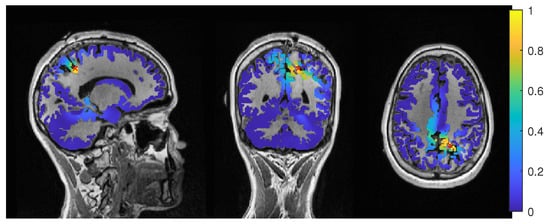

The results for Patient 1 are shown in Figure 3. It should be noted that jumps in the distance measure do not mean large differences in the localization distribution. The beamformer power is not focused on a single spot, but positions with nearly the same power are distributed around it, see Figure 4 or Figure 5, for an example. With changing regularization, these points are weighted differently and the maximum can shift from one to another, leading to a jump in the distance to the resection. There were overall rather low distances for the EEG.

The average-based beamformer showed distance values below 5 mm for nearly all regularisation parameters and localized into the resection volume for both 6C and 3C head models when using a regularization parameter of 0.04. To better understand why results do not change smoothly with the regularization parameter, we present in Figure 4 the results for a parameter of 0.04, where the maximum point with maximum power of the localization is inside the resection, but the surrounding points are on the border with nearly the same power. With variations in the regularization, the maximum shifted around these points and gave a localization outside, which explains the changes observed in the distance to the resection volume. As Figure 3 also shows, the localization for the 6C model was inside the resection for all regularization values above 0.142. With a relative power relation value of close to 1, both models showed high uncertainty for regularization parameters above 0.1.

Except the cases of no regularization and average beamforming in the 6C head model, the differences of the evaluated methods in the distance to the resection volume for the MEG were overall lower than for the EEG. The event-related beamformer in both 6C and 3C head models showed localizations in the resection volume (localization distance of 0 mm) for the main part of evaluated regularization values. The 3C model’s localization distance increased slightly for the higher parameter value choices above 0.128. The 3C model’s power outside the resection was nearly the same as inside, resulting in a power relation close to 1, while the 6C model showed some certainty, with a power relation between 0.96 at low regularization values and 0.92 for high values. Both relations were not strongly affected by regularization. The localization of the 6C model at 0.05 regularization on the inside of the resection border is shown in Figure 5. While the maximum was inside the resection, the signal spread to the middle of the head to some degree.

The average-based beamformer performed worse for both models. Except for very low regularization parameters, the 6C model showed a distance of 6 mm, while the 3C model was at 2 mm. For the regularization parameters from 0.002 to 0.01, the 3C model localized into the resection. No regularization resulted for both models at high distances. The 6C model’s relative power was rather high, giving it a certain localization outside the resection. The 3C model’s relative power switched between a certain localization inside the resection for the low regularization parameters to a very certain localization outside for higher parameters, showing the importance of regularization strength.

The dipole scan in the 6C head model (Dip-6C in Figure 3) localized 4 mm outside the resection, while the 3C scan (Dip-3C) was 2 mm away. Their gof was 88% and 80%, respectively, with very high uncertainty for both as the relative power was close to 1.

As shown in the third row of Figure 3, MEEG performed with rather low distances to the resection volume for most methods, but could not reach 0 mm for most parameters.

The 6C event-related beamformer’s distance to the resection volume was 16 mm or 19 mm for the main part of the regularization parameters. Similarly, the 3C model showed a distance above 18 mm for all parameters. Both showed high certainty in their localization.

The 6C averagebased beamformer’s localization distance to the resection volume was with 4 mm distance lowest for regularization parameters between 0.026 and 0.046, while it was considerably higher outside this range. Its relative power showed some variation, but gave certainty to the localization outside the resection for nearly all parameters. The 3C model’s distance to the resection volume showed a large variation for low regularization parameters between 0 and 0.01. For those parameters above 0, the power relation hints at 2 spots with similar power, one inside the resection volume and one 25 mm away from it. The localization stabilized for regularization parameters above 0.036 with a distance to the resection volume of 2 mm.

The dipole scan in the 6C head model (Dip-6C in Figure 3) localized 6 mm outside the resection with gof of 90% and some certainty. The 3C dipole scan (dip-3C) peaked inside with a gof of 80%. Points with high gof closely followed the resection outline, although it crossed the border and thus had a high relative power close to 1. The 3C dipole scan is shown in Figure 6.